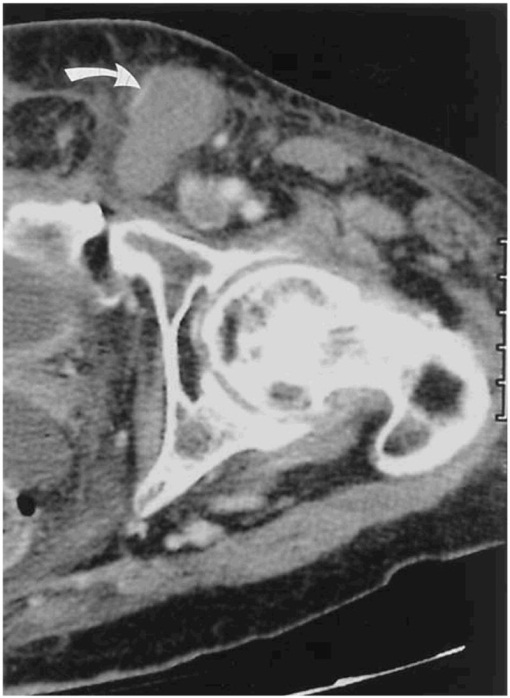

Bệnh nhân nữ, 58 tuổi, tiền sử ung thư ống vòi trứng> 2 năm.

A. Khối di căn phần mềm vùng bẹn trái, kèm huyết khối tĩnh mạch đùi (mũi tên đen), khối ngấm thuốc mạnh sau tiêm (mũi tên trắng).

B. Khối phần mềm sau khi đốt sóng cao tần không còn ngấm thuốc sau tiêm.